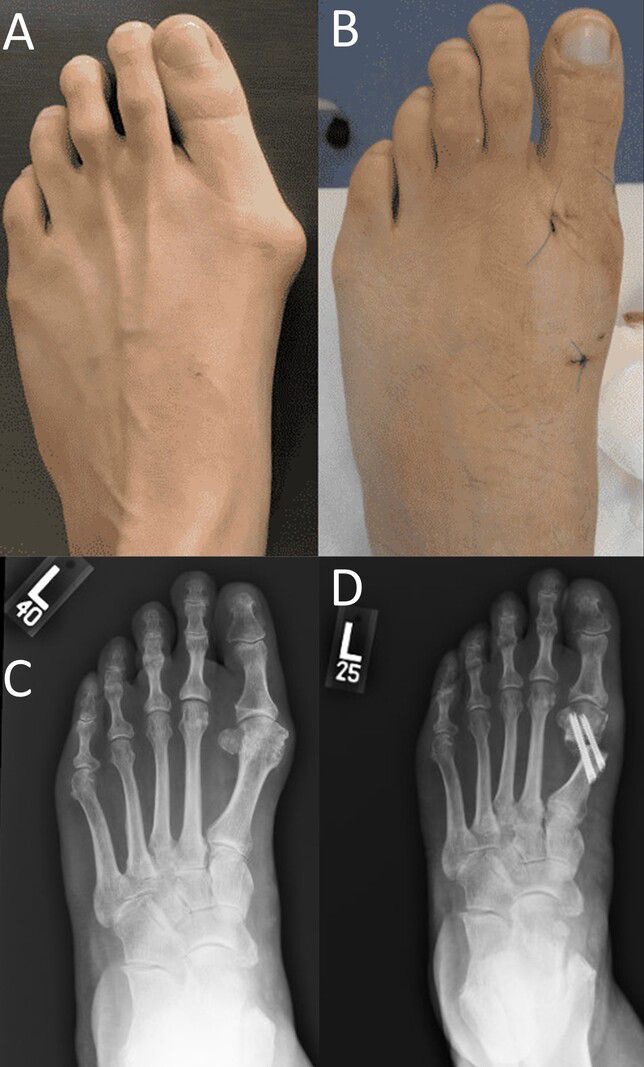

"Operar os dois pés e pisar imediatamente!” esse lema gerou resultados incríveis no tratamento do pé plano e do joanete. Conheça as técnicas que foram apresentadas pelo Dr Rodrigo Astolfi na Itália (pé plano) e na Coréia do Sul (joanete).